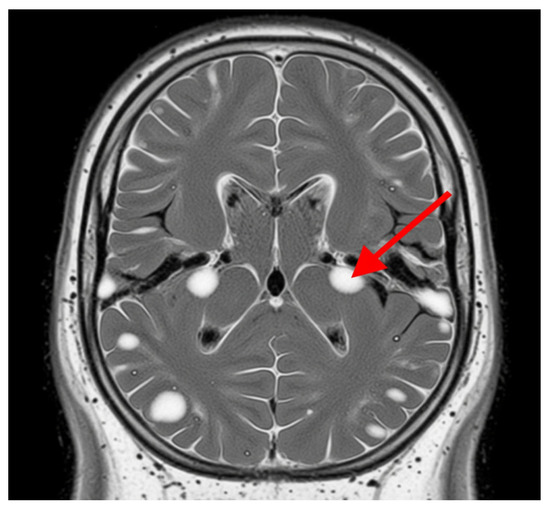

Advanced MRI techniques have enhanced the capacity to identify and characterize these lesions, providing valuable insights into their evolution and their relationship with clinical outcomes. The persistent and expanding nature of white matter lesions highlights their central role in SPMS pathophysiology and underscores the importance of longitudinal MRI studies for monitoring disease progression and therapeutic response, Figure 2 [38].

Figure 2. White matter lesions. The grey area represents the brain tissue, and the bright white areas represent the white matter lesions. These lesions are typically hyperintense (brighter) on T2-weighted MRI scans and represent areas of damage to the myelin sheath, which insulates nerve fibers in white matter. The red arrow indicates one of these distinct bright white lesions. In SPMS, these lesions indicate demyelination, axonal loss, and gliosis.